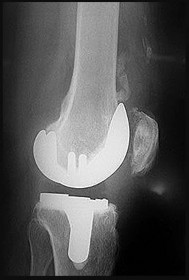

Question 16:

A 65-year-old man presents with anterior knee pain and a feeling of instability during stair climbing 1 year after a primary total knee arthroplasty. Examination reveals a lateral patellar tilt. CT scan is performed to evaluate component rotation. Which of the following errors in component positioning is most likely responsible for his symptoms?

Correct Answer: Internal rotation of the femoral component

Explanation:

Internal rotation of the femoral component or the tibial component increases the Q angle, leading to lateral patellar maltracking, lateral patellar tilt, and anterior knee pain. External rotation of the components generally improves patellar tracking.